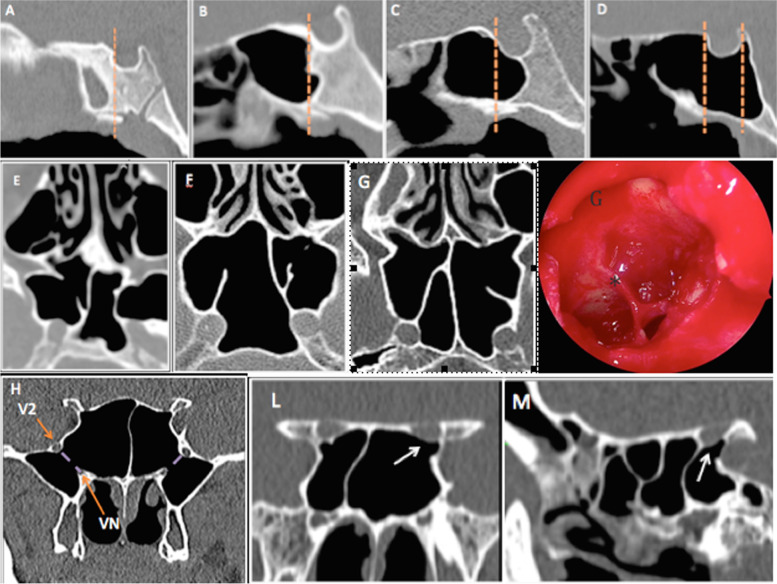

Based on the CT images, the following variables were assessed: type of SSP, protrusion and dehiscence of the ICA and/or ONC, position and attachment of IS onto these structures, presence of AS and PRP (Fig. 1).

Fig. 1.

Güldner’s classification7 of sphenoid sinus pneumatization on sagittal CT images: A conchal, B presellar, C sellar, and D postsellar pneumatization types. Axial CT images showing (E) right dehiscent internal carotid artery (ICA) and protrusion of accessory sphenoid septa into the left ICA, F deviation of the sphenoid septum in left ICA protrusion, G accessory septations with attachment on the right ICA; G endoscopic right sphenoid sinus show an accessory septations (*). Coronal (H) CT image revealing bilateral pterygoid recess pneumatization. Coronal (L) and sagittal (M) CT scans showing dehiscence of the left optic nerve (ON) and attachment onto the sphenoid sinus (white arrow)